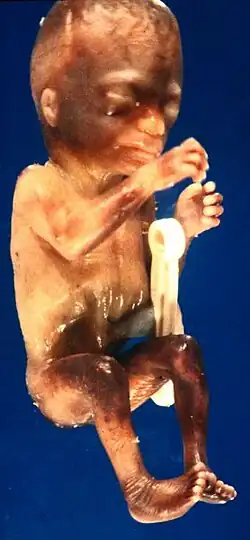

Feto humano

Feto humano